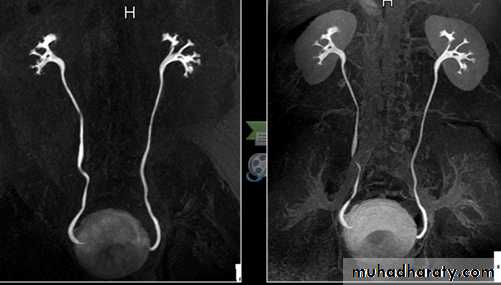

Renal MRA

-PCS, ureter and bladder are best seen by T2 .

-Heavily weighted T2 is used to acquire MRU.

• Renal artery stenosis